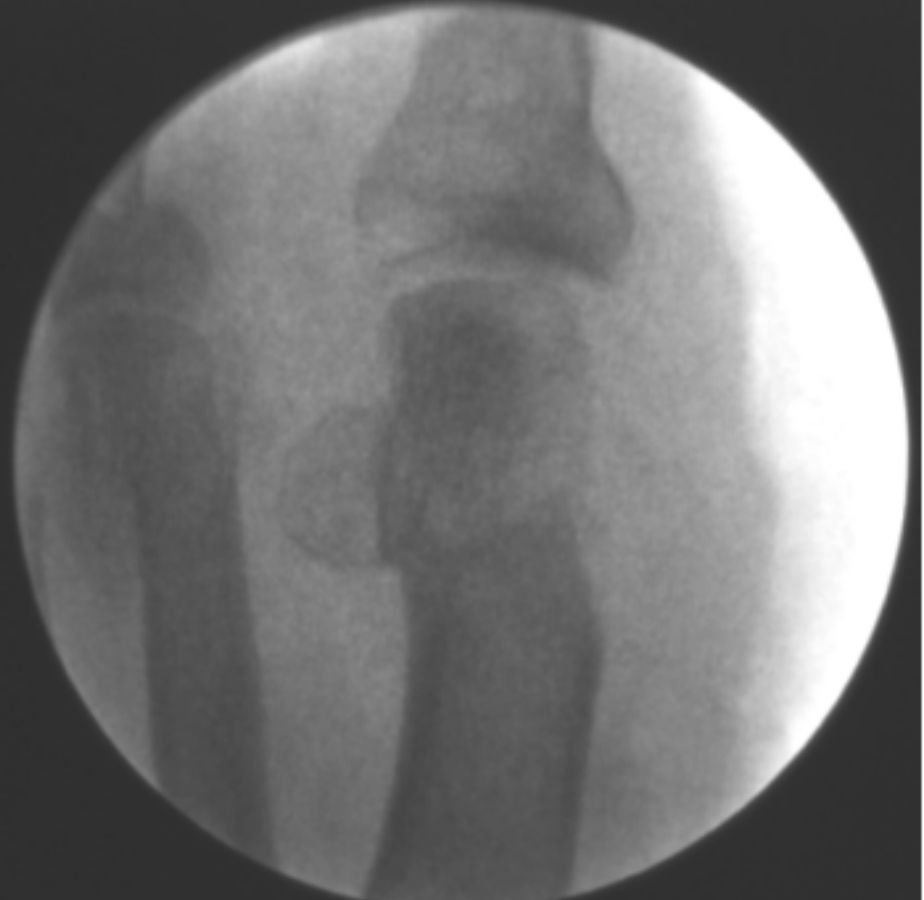

ANTES

casos reales juanetes alicante (6)